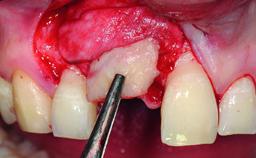

A healthy 38-year-old male patient was referred for replacement of a failing tooth-supported cantilever fixed dental prosthesis on teeth 11 and 21. The patient reported a history of trauma at 13 years of age that had resulted in the subsequent loss of tooth 11, as well as endodontic treatment of the adjacent abutment tooth 21. A metal-ceramic cantilever fixed dental prosthesis replacing tooth 11 had been provided by his general dentist several years after the loss of the tooth, with tooth 21 as the sole abutment. At the time of initial presentation, this restoration had been in service for over 20 years.

Bone Volume | Deficient horizontally, allowing simultaneous augumentation |